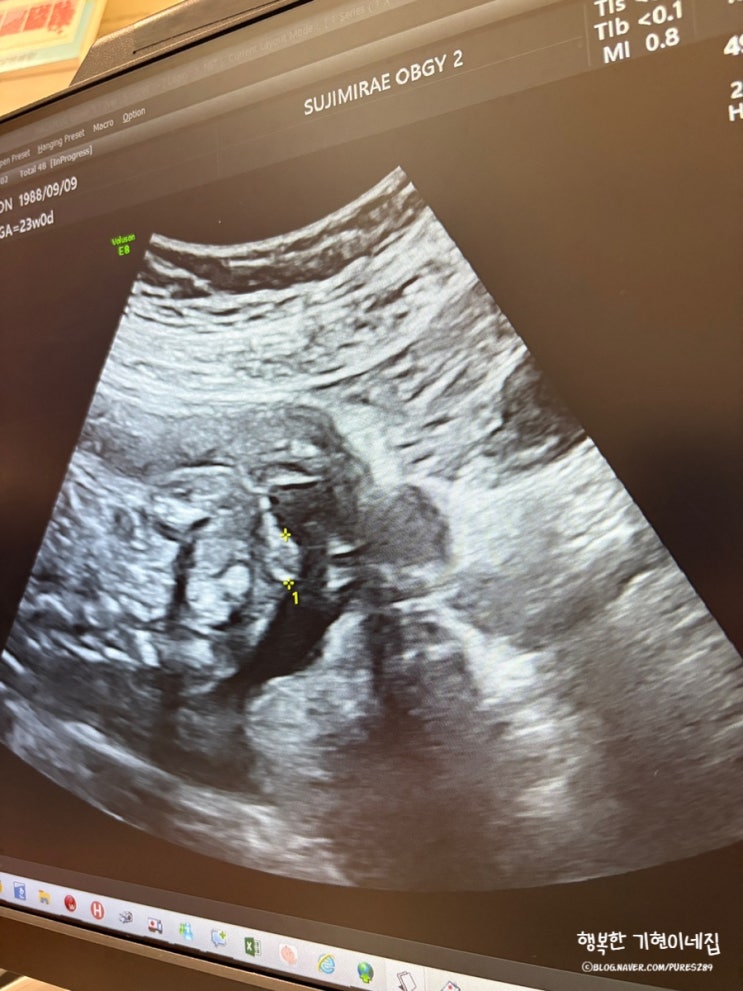

태아 꼬리뼈 혹 아산병원 태아치료센터 원혜성 교수님 엉덩이 스킨텍

오늘은 임산부인 엄마를 천당과 지옥으로 오가게 했떤 1주간의 이야기를 써보려고해요. 이 글이 누군가에게...